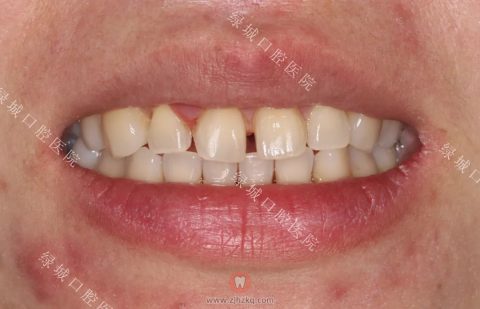

这是一个门牙畸形的患者,因为大门牙关系到一个人的整体形象,为了美观做了全瓷贴面,效果还是很棒的。

患者牙齿治疗前